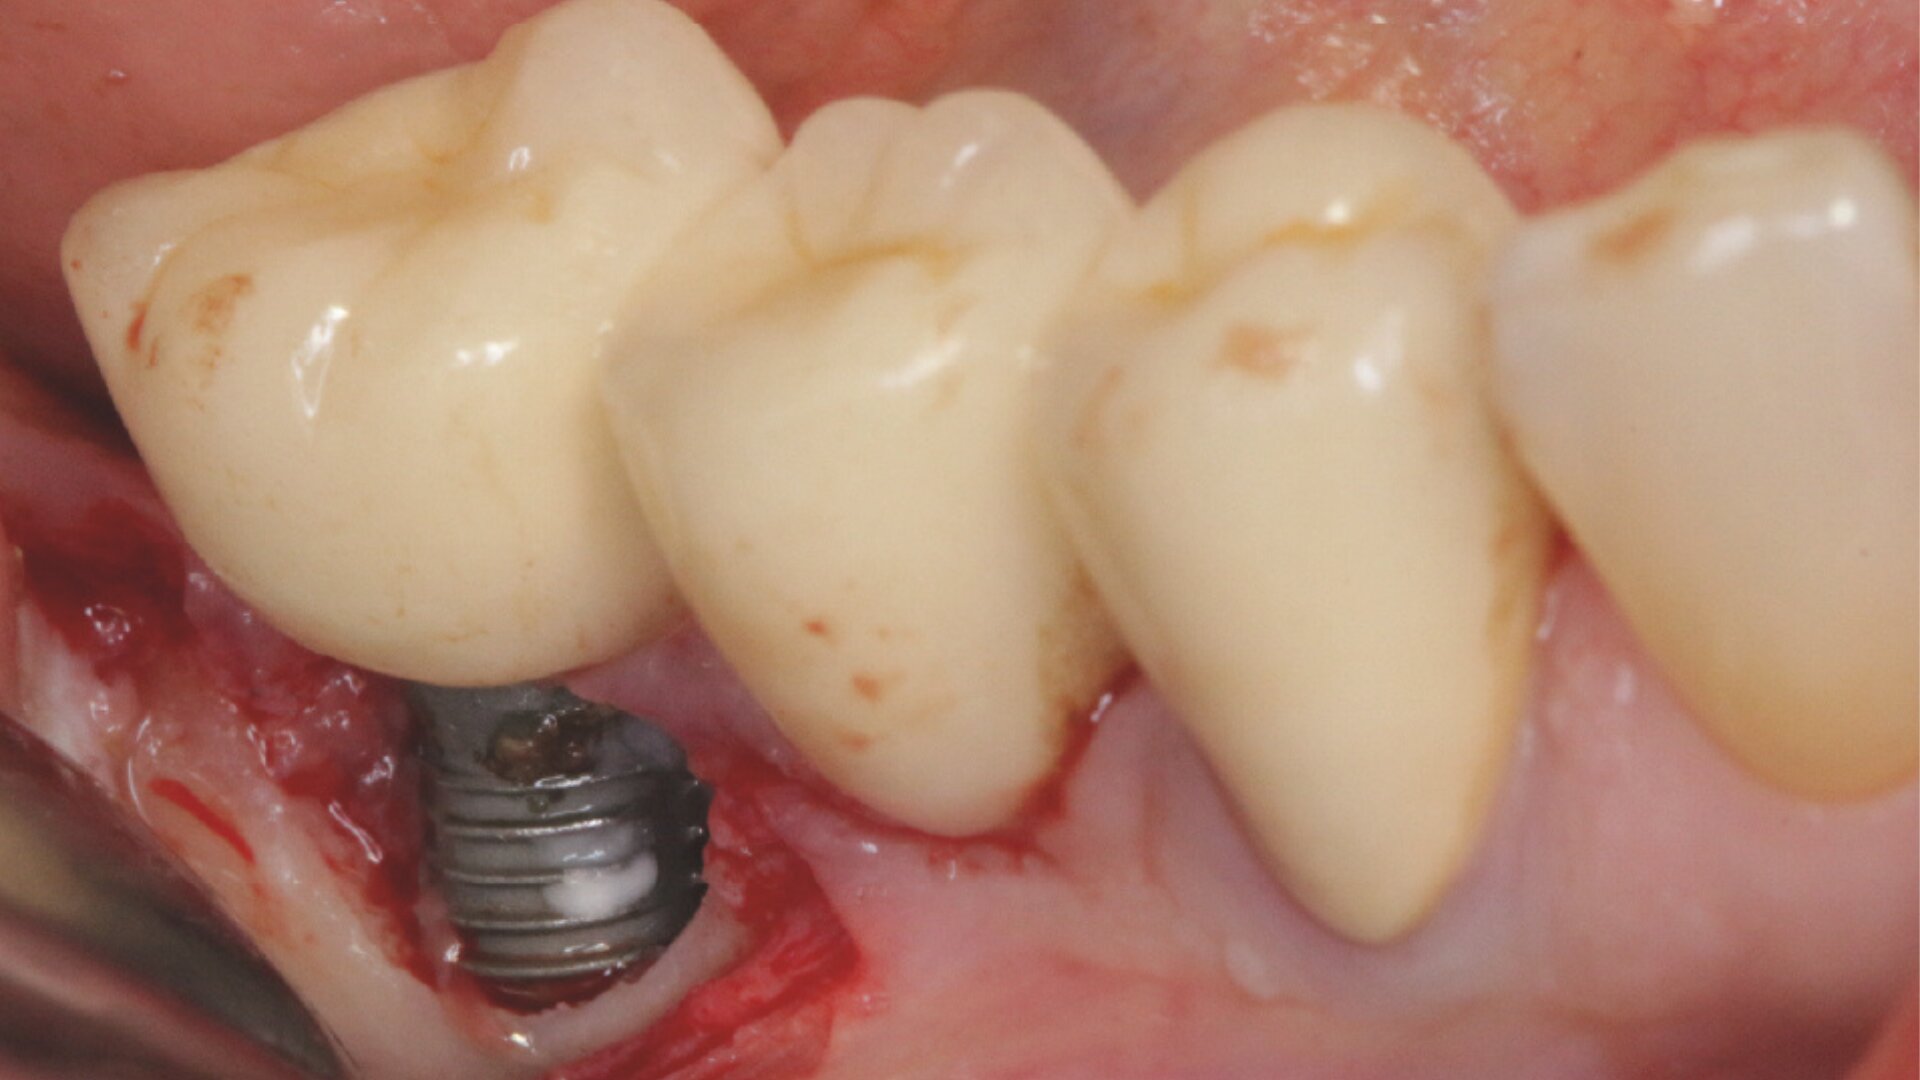

Die Implantologie hat sich als fester Bestandteil moderner zahnmedizinischer Therapie etabliert. Langfristiger Implantaterfolg hängt jedoch maßgeblich von einer konsequenten prävention periimplantärer Erkrnakungen ab. Dieses Webinar bietet einen kompakten Überblick über aktuelle wissenschaftlicher Erkenntnisse und praxisnahe Strategien zur periimplantären Prophylaxe. Behandelt werden Risikofaktoren für periimplantäre Mukositis und periimplantitis, aktuelle Empfehlungen zur professionellen Nachsorge sowie Instrumente und Materialien für eine effektive Biofilmentfernung. Darüber hinuas werden wissenschaftliche Erkenntnisse zur häuslichen Individualprophylaxe vermittelt.